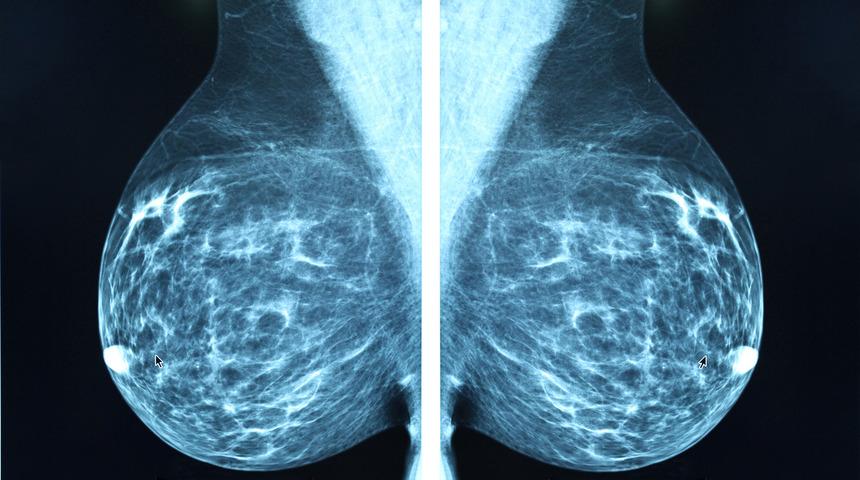

Google, bu algoritmanın geliştirilebilmesi için Hollanda'daki bir top merkezinden aldığı veri kümesini kullandı. Söz konusu veri kümesinde meme kanseri hastalaraının lenf bezi taramaları bulunuyor

Patalogların işlediği bu girdiler meme kanseri hastalarının lenf bezlerinden alınan doku örnekleriyle birlikte analiz edildi. Analiz edilen bu bilgiler sayesinde kanser hücresinin ne kadar agresif bir ilerleme kaydettiği ve vücudun ne kadar yayılmış olabileceğini ortaya koyuyor.

Algoritmanın çalışma doğruluğunun verildiği bilgilere göre, metastaz (kanserli hücrelerin bulundukları doku dışında doğrudan ya da kan-lenf damarlarıyla başka bölgelere sıçraması) evresindeki hastaların yüzde 99'unda kanser teşhisinde başarı söz konusu.